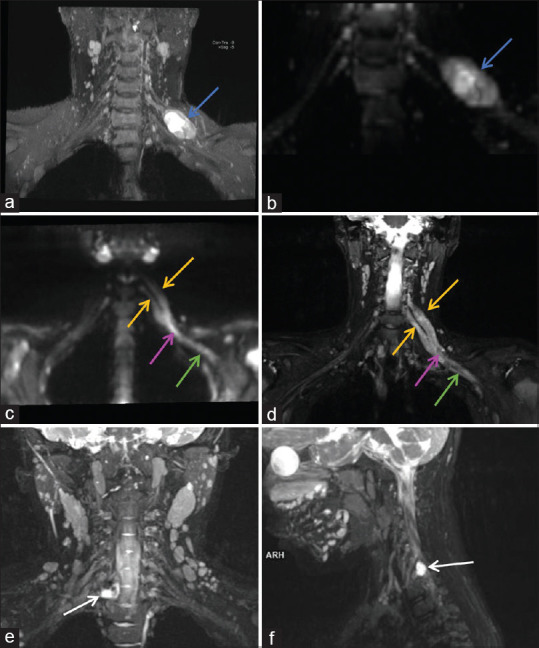

背景和目的:磁共振神经成像(MRN)允许神经的直接可视化,这可以有助于周围神经疾病的诊断、表征和定位。我们计划对转介行核磁共振的周围神经损伤患者进行研究,并将核磁共振结果与神经传导研究(NCS)对各种局灶性神经疾病的结果进行比较。方法:这项前瞻性研究进行了超过1年半,涉及58名临床诊断为局灶性周围神经病变的受试者,他们被转介到放射诊断和影像学部门进行MRN检查。MRN检测到的局灶性周围神经病变范围与NCS和/或肌电图结果以及手术和/或组织病理学结果相关并进行比较。采用χ 2检验和Fisher精确检验评价MRN与NCS结局的相关性。结果:该研究确定了广泛的周围神经病变。在58例受试者中,52例(89.6%)发现异常,而6例(10.3%)患者未显示任何明显异常。50例(86.3%)患者在MRN和NCS上均表现异常,5例(8.6%)患者在MRN和NCS上均未表现异常。2例(3.4%)MRN异常但NCS结果正常,1例(1.7%)MRN正常但NCS结果异常。在58例mri检查中,25例发现臂丛受累。结论:核磁共振成像是评价周围神经病变的一种高度敏感的工具。其与NCS和术中发现的相关性进一步支持了其临床应用。在周围神经病变的诊断过程中,3t核磁共振成像应被视为一种关键的成像方式。此外,它还可以作为规划治疗干预措施和评估各种患者亚群预后的有价值的指南。

Results: The study identified a broad spectrum of peripheral nerve pathologies. Out of 58 subjects, abnormalities were found in 52 (89.6%) subjects, whereas six patients (10.3%) did not show any significant abnormalities. Fifty patients (86.3%) showed abnormalities on both MRN and NCS, while five patients (8.6%) did not show any abnormalities on either MRN or NCS. Two patients (3.4%) showed abnormalities on MRN but had normal NCS results, and in one case (1.7%), MRN was normal but NCS showed an abnormality. Out of the 58 MRN examinations, 25 were found to have brachial plexus involvement.